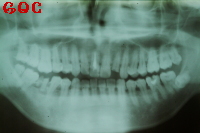

▼治療前![]() |